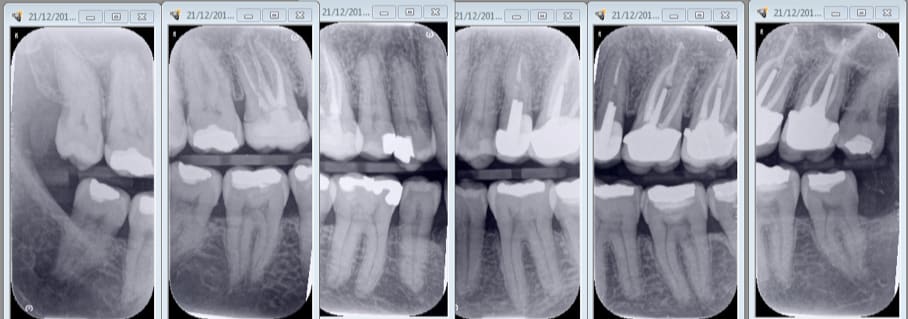

taille 3 vertical. Un seul angulateur qui fait tout avec tous les films droite gauche haut et bas en fonction de la position du film. . Dentsply pour capteur en rétro coronaires Vertical à la base. Ergonomie ++++

Haut et bas sans modifier l'angulateur. Seulement la position du film. Ici taille 2.